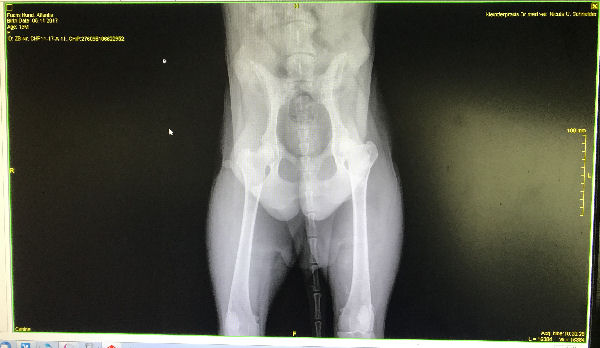

Atlantis - HD-Röntgen

img_5240-hd-Atlantis-hd